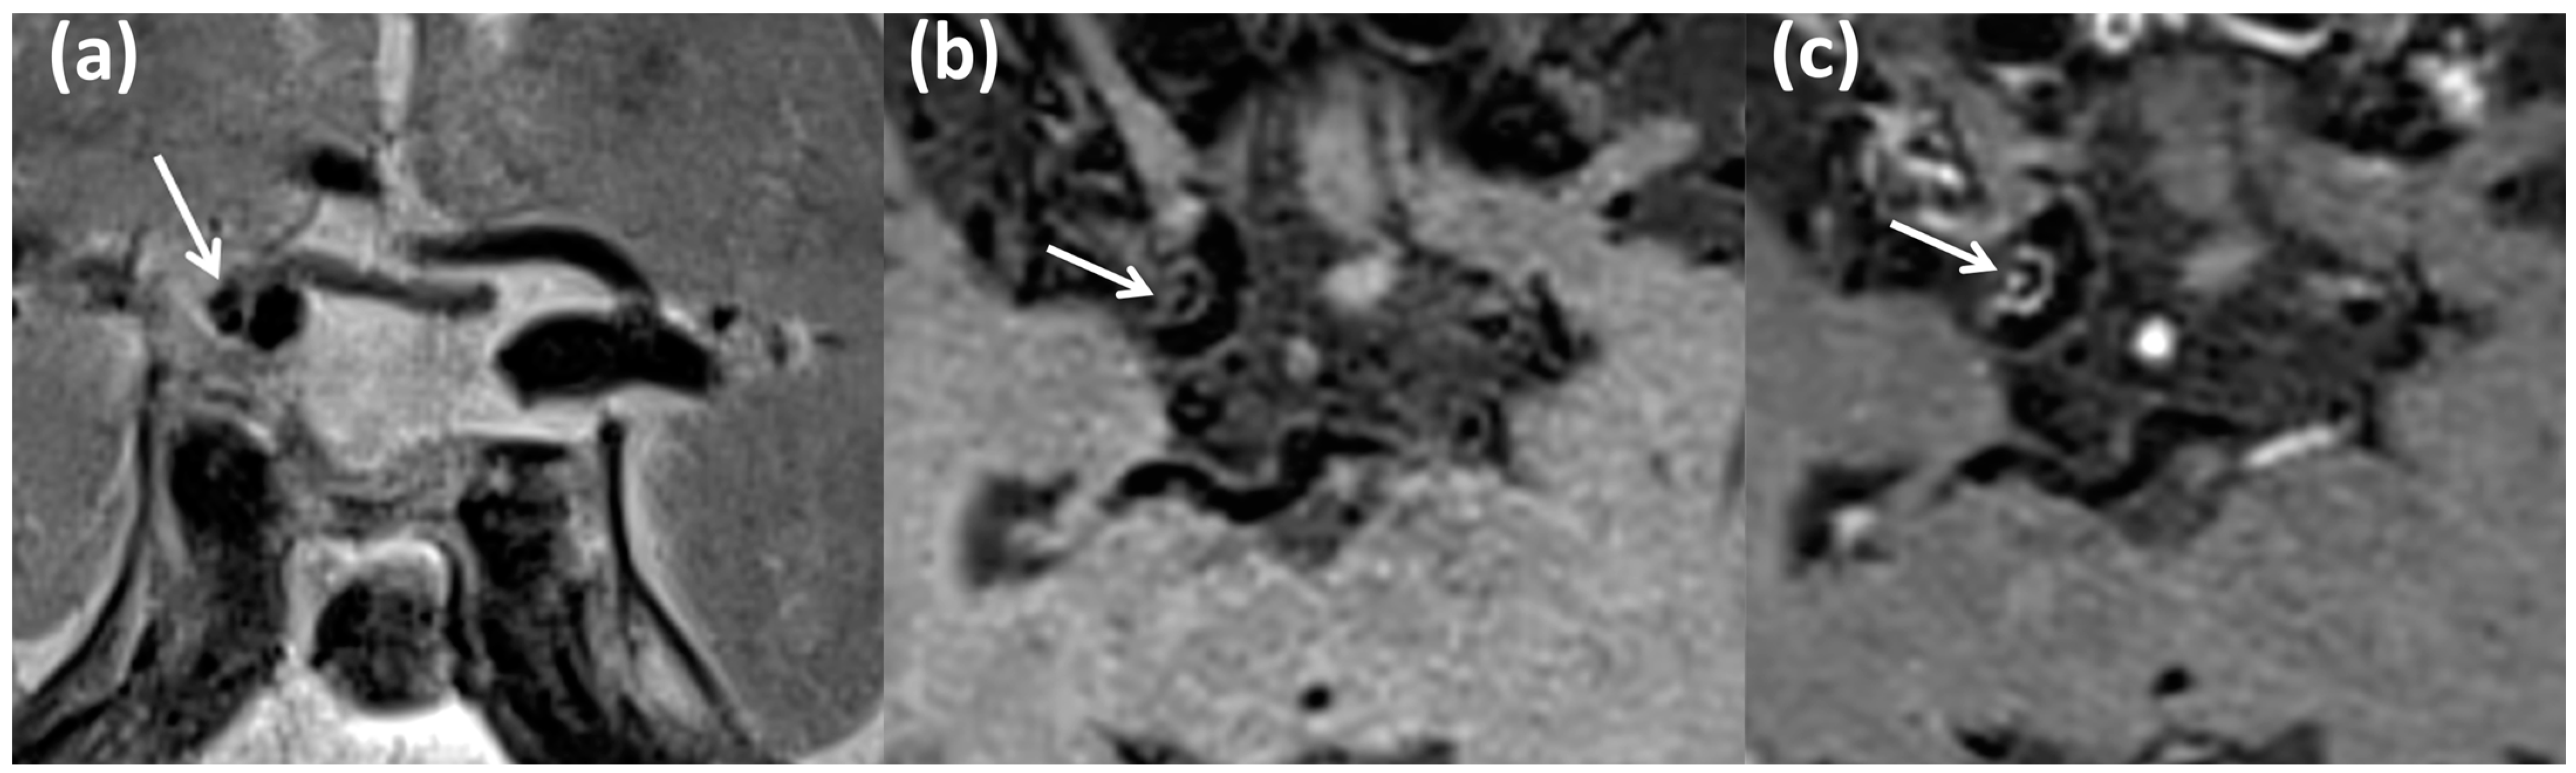

- Kang, D.W.; Kim, D.Y.; Kim, J.; Baik, S.H.; Jung, C.; Singh, N.; Song, J.W.; Bae, H.-J.; Kim, B.J. Emerging Concept of Intracranial Arterial Diseases: The Role of High Resolution Vessel Wall MRI. J. Stroke 2024, 26, 26–40. [Google Scholar] [CrossRef] [PubMed]